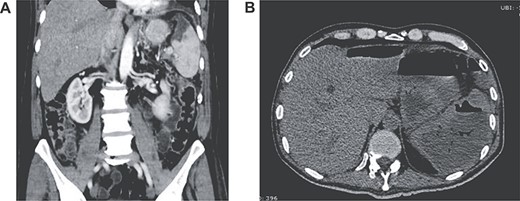

Patient is a 58-year-old male, with past medical history of pancreatogenic diabetes and cholecystectomy. He presented to the emergency room with a 2-day history of severe episodes of bright red blood stool, abdominal pain and difficulty breathing. Initial evaluation revealed a dehydrated, tachycardic, hypotensive and confused patient. Complete blood count revealed severe anemia (Hb 6.5 mg/dl), lactate was 5 mmol/L, bicarbonate was 12 meq/L and creatinine level was 3.5 mg/dl. Liver chemistries were mildly elevated and the coagulation profile was normal. He was admitted to the intensive care unit (ICU), and treated with vigorous volume resuscitation, transfused 4 units of blood and vasopressors. Colonoscopy was needed nonetheless it was inconclusive as the bleeding site could not be recognized. With these findings, an enhanced abdominal computed tomography (CT) was requested revealing a 10 × 11 mm aneurysm of the left colic artery. Angiography was performed and a transcatheter arterial embolization successfully controlled the bleeding. The patient improved, vasopressors were phased out and he was discharged without any apparent complications (Fig. 1).

(A) Contrast-enhanced CT showing splenic infarction with inflammatory changes; (B) CT showing free liquid with a hypodense lesion.